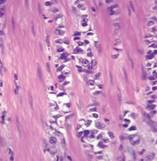

Al cuarto día del ingreso por persistencia de los síntomas y deterioro del estado general del paciente se practicó estudio radiográfico de estomago con contraste iodado hidrosoluble (figura 2) que mostró una volvulación gástrica mesentérico-axial  incompleta.

Fig. 2. Estudio radiográfico de estomago con contraste iodado hidrosoluble  que mostró una volvulación gástrica mesentérico-axial incompleta.

El estudio radiográfico gástrico muestra la entrada de la sonda nasogástrica al cardias en el contorno inferior de la proyección del estómago, definiéndose en la vista de Hampton los pliegues irregulares a este nivel propios del fundus, lo que indica rotación en el eje mesenteroaxial, permitiendo el paso de contraste que da aspecto en reloj de arena, propio de la volvulación incompleta del estómago.

Además se observa hacia la parte superior del estómago el contorno de un asa, donde el aire hace función de contraste, en relación con el duodeno, por lo tanto estamos en presencia de una volvulación mixta. El paciente fue intervenido quirúrgicamente detectándose que la causa de la volvulación era una brida adherida al fundus gástrico que lo unía a asas yeyunales, con un mega estómago que presentaba hipotonía y adelgazamiento de la pared.